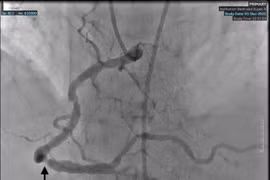

Cụ ông phải cắt cụt chi dưới vì xơ vữa động mạch gây tắc, hoại tử

Bệnh xơ vữa động mạch chi dưới tiến triển âm thầm, cần phát hiện sớm để tránh hoại tử và cắt cụt, đặc biệt ở người cao tuổi.